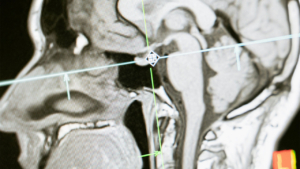

A centralized resource hub dedicated to Medical Imaging and Radiology, providing extensive industry insights and a diverse collection of articles on essential topics. This platform aims to serve as an invaluable resource for healthcare professionals by delivering informative content on various imaging modalities, the latest advancements in radiological technology, best practices for patient care, and emerging trends in the field of medical imaging.